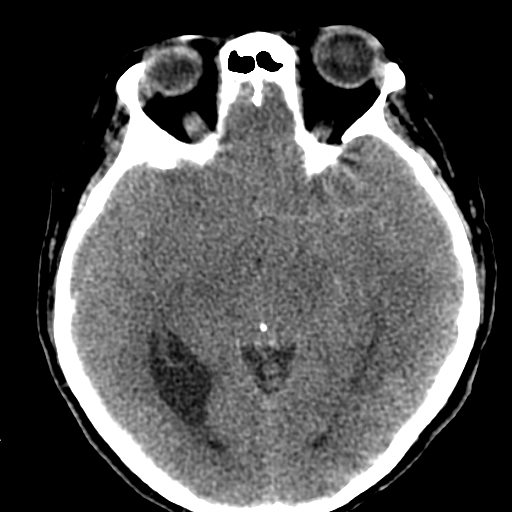

Больному около 55 лет, клинику дает не сколько само образование, а компрессия структур мозга, базально вообще беда (отчасти видно компреммию некоторых базальных цистерн мозга). Сразу скажу насчет эпидермоидной кисты - ДВИ не будет :)

На объем как то тоже не похоже. , сигнал равномерный и такой же как и от ликвора. Если расценивать как последствия ОНМК так это как должно было " рвануть" да еще и с поражением желудочков - не пациент бы вряд ли выжел. Как же сложно в этом к/т ! Не знаю может это глупо, но у меня пока впечатление о врожденной патологии мозга. А с контрастом не делали ? Или вам и так все понятно, Сергей Николаевич , тогда поделитесь мыслями пожалуйста.

Да, это негатив КТ, специально для Танюши, чтобы проще сориентироватся.